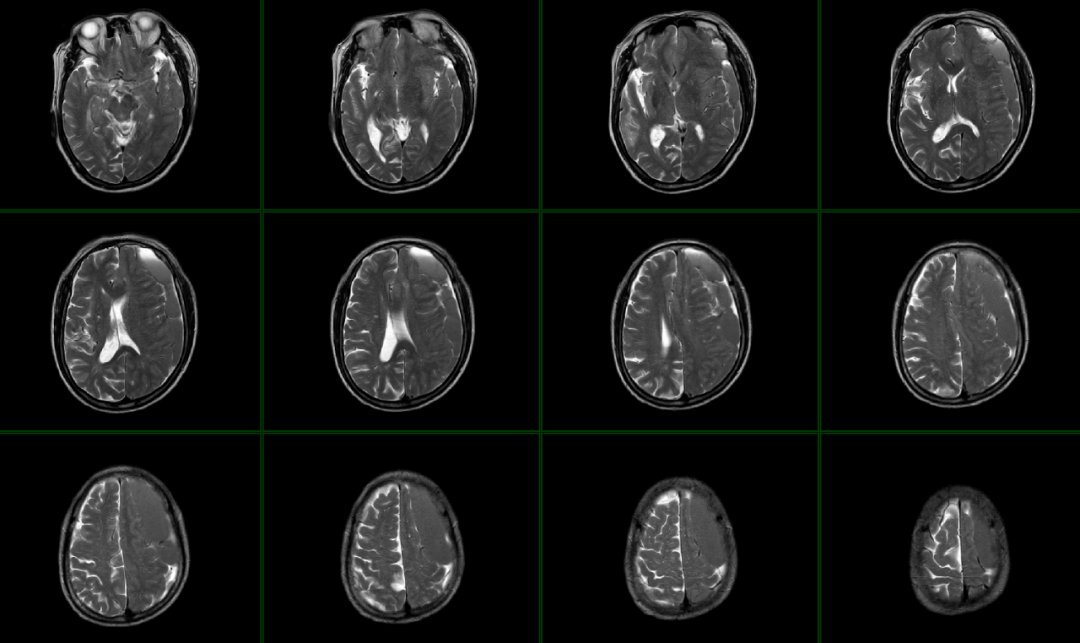

头颅MR:左侧额颞顶枕部硬膜下血肿,颅内多发陈旧性脑梗塞。

慢性左侧额颞顶枕部硬膜下血肿

术后第一天头颅CT(2019年9月13日):左侧额颞顶部血肿清除满意,颅内少量积气。术后第三天2019.9.15拔除术区引流管。

术后第9天复查头颅CT(2019年9月21日):颅内情况良好,颅内积气明显吸收减少。

2019年9月23日复查头颅CT:慢性硬膜下血肿术后改变,左额部少量积气。排除硬膜下血肿复发及脑组织肿胀、缺血等表现。

头颅MR(2019年9月26日):脑组织未见挫伤、缺血、急性脑梗死等表现。